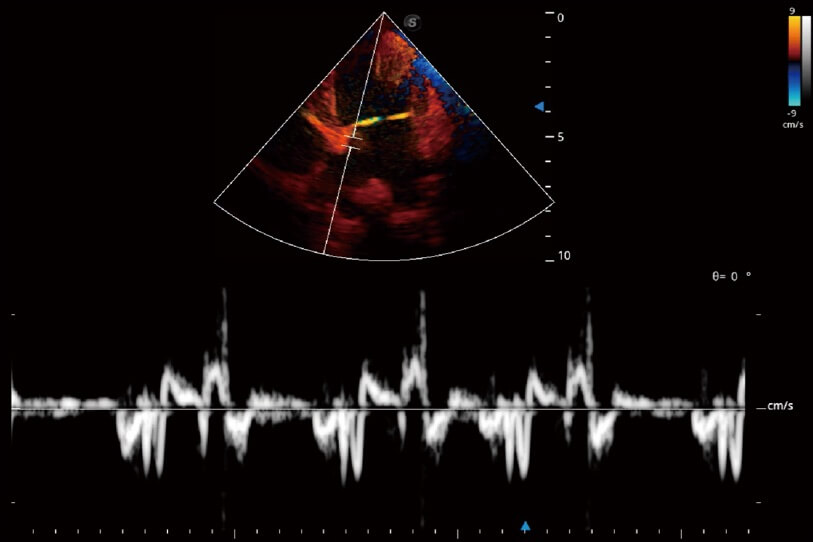

實(shí)時(shí)用顏色表示心肌組織運(yùn)動(dòng),觀察和定量組織的運(yùn)動(dòng)情況,對(duì)快速檢測(cè)與評(píng)估心肌的灌注和活性、電傳導(dǎo)及心肌收縮和舒張功能等均能提供重要的診斷信息。